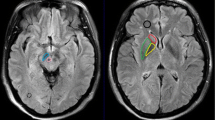

The influence of iron deposits on T2 values and the content of metabolites in the brain of three patients with DNA proved pantothenate kinase-associated neurodegeneration (PKAN, formerly Hallervorden-Spatz syndrome) was studied. An eye-of-the-tiger sign, a typical MR finding for PKAN, was observed in two patients with the same mutation. A hypointensive lesion in a whole globus pallidus was observed in the third patient with the additional mutation. T2 values in the globus pallidus of the patients were about 40% shorter than in controls (71/48 ms in controls vs. patients), which corresponds to the increase of Fe concentration based on the ferritin basis from 17 mg for controls to 48 mg (100 g wet brain weight) in PKAN patients. 1H MR spectroscopy (MRS) has mainly been used to describe neuronal damage represented by decreased NAA (6.4 mmol vs. 9 mmol) and Cr/PCr (7.0 mmol vs. 9.8 mmol) concentrations in the basal ganglia region of the patient group to controls; MRS is much more case-sensitive and describes individual development of the disease as demonstrated in the difference between the spectra of typical PKAN patients (1, 2), and the patient (3) with atypical PKAN development. Any significant changes of metabolite concentration with the exception glutamine, glutamate and GABA were found in the white matter.